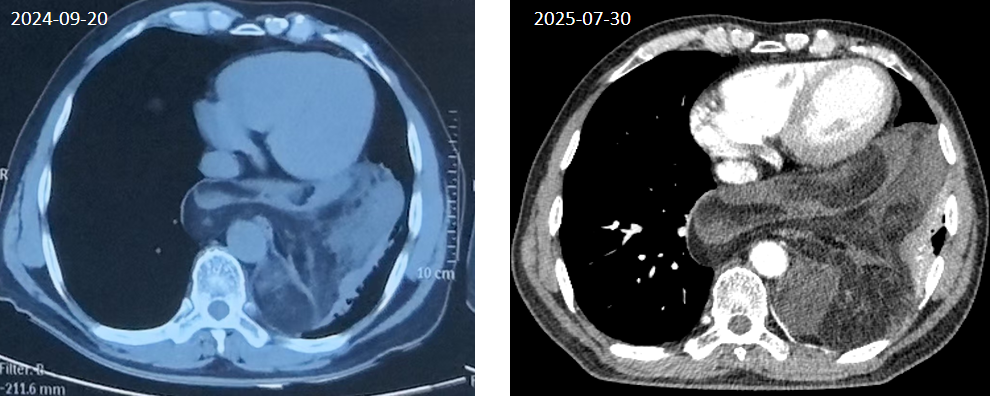

患者老王怎么也没想到,一年前一次常规体检,竟在他体内发现了一颗“定时炸弹”,后纵隔有一个12cmX13cm的肿物,以脂肪密度为主。“这么大个东西,我咋一点感觉没有?”老王看着报告,心里虽有嘀咕,但身体确实没有任何不适。他觉得不痛不痒,便没太当回事,选择了“观察”。然而,他不知道,这个潜伏在胸腔“核心区”的肿瘤,正悄然生长,准备掀起一场风暴。

一年后,平静被打破。老王逐渐开始出现血压升高、心率减慢等奇怪的症状。身体发出的警报让他不敢再拖延,老王来到北京清华长庚医院胸外科主任陈东红的门诊寻求帮助。CT检查显示当初那个12厘米的肿物,如今已进一步明显增大,长到18cmX15cm,几乎有一个足球那么大!

这个肿瘤不仅巨大,位置更是刁钻——深藏于后纵隔,这里是心脏、大血管、食管、神经等重要器官的“中央办公室”。影像片上,肿瘤挤压左下肺导致肺不张,并推挤着心脏、膈肌和降主动脉、下腔静脉等大血管,甚至有侵犯的迹象。曾经“沉默”的杀手,如今已“张牙舞爪”,严重威胁着老王的生命。